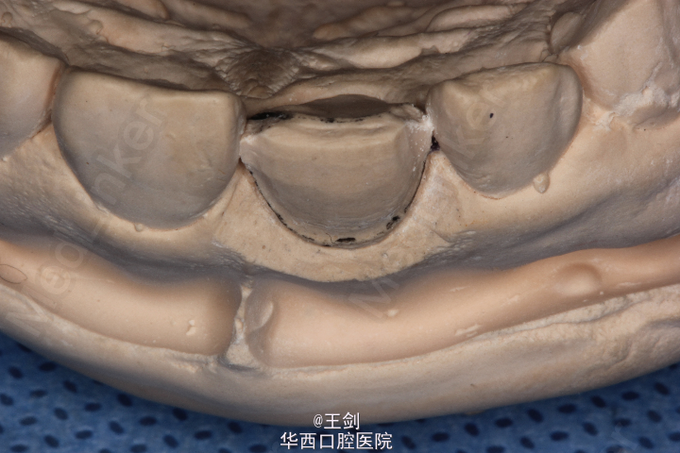

CAD/CAM瓷贴面修复一例

11牙因外伤缺损,未露髓。

拟行CAD/CAM贴面修复11牙,当天备牙,当天戴牙

CAD/CAM 技术制作贴面可以达到高度密合,大大节省诊疗时间等优点